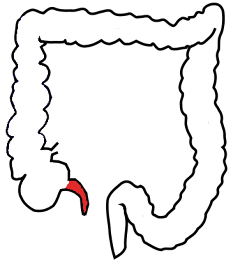

Harry Houdini died of peritonitis caused by a ruptured appendix on October 31, 1926, at Grace Hospital in Detroit. He was 52. The rupture is popularly attributed to punches delivered by a college student nine days earlier, though physicians debate whether blunt trauma can actually cause appendicitis. Houdini had ignored symptoms for days and continued performing with a 104-degree fever. The timing of his death on Halloween was coincidental but fitting: Houdini had spent his final years debunking fraudulent spirit mediums and exposing their tricks. Before his death, he told his wife Bess a secret code they would use if he could contact her from beyond the grave. She held seances on Halloween for ten years. The code was never received. 'I do not think that Houdini will come back,' she finally said.